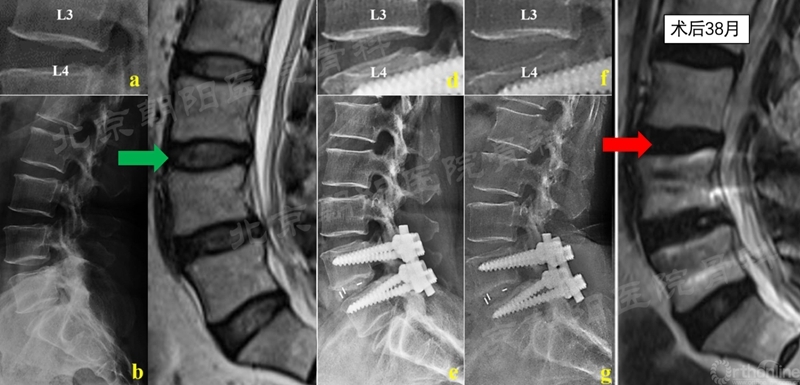

典型病例2.PS-PLIF术后患者38月随访复查MRI,邻近节段椎间盘出现明显退变,Pfirrmann分级1->4级,椎间隙高度下降。